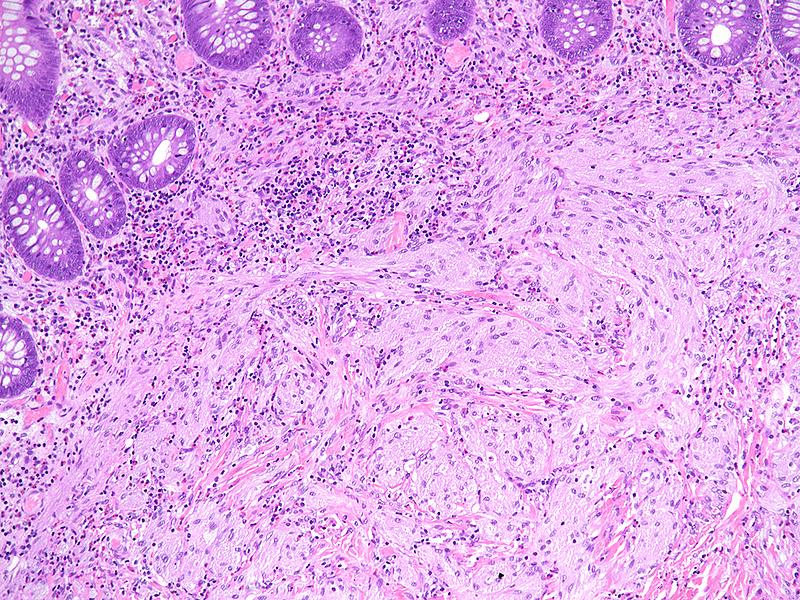

Histologically, we saw a submucosal proliferation of solid nests and ribbons of round to polyhedral cells, measuring approximately 6 mm in largest diameter (Panels A-B). The neoplastic cells generally contained small, uniform nuclei with inconspicuous nucleoli and abundant granular eosinophilic cytoplasm. They were separated by fibrous septa, which contained few inflammatory cells, mostly lymphocytes and few eosinophils (Panel C). In some areas, the neoplastic cells demonstrated cell spindling, still keeping the cytoplasmic features described above (Panel D). The lesion was ill-defined at the base, showing an infiltrative pattern into the surrounding adipose tissue within the submucosal layer (Panels E-F). The neoplastic cells were positive for PAS and strongly immunoreactive for S100-protein (Panels G-H), yet negative for keratin, CD117, DOG-1, and muscle markers, prompting final diagnosis of colonic granular cell tumour.

Behaviour is almost invariably benign, but patients may experience recurrence after incomplete excision. Reactive changes of the oerlying epithelium may be observed, mimicking a neoplastic process. This is an important pitfall within the oesophagus, but does not usually pose larger problems in the colorectum.